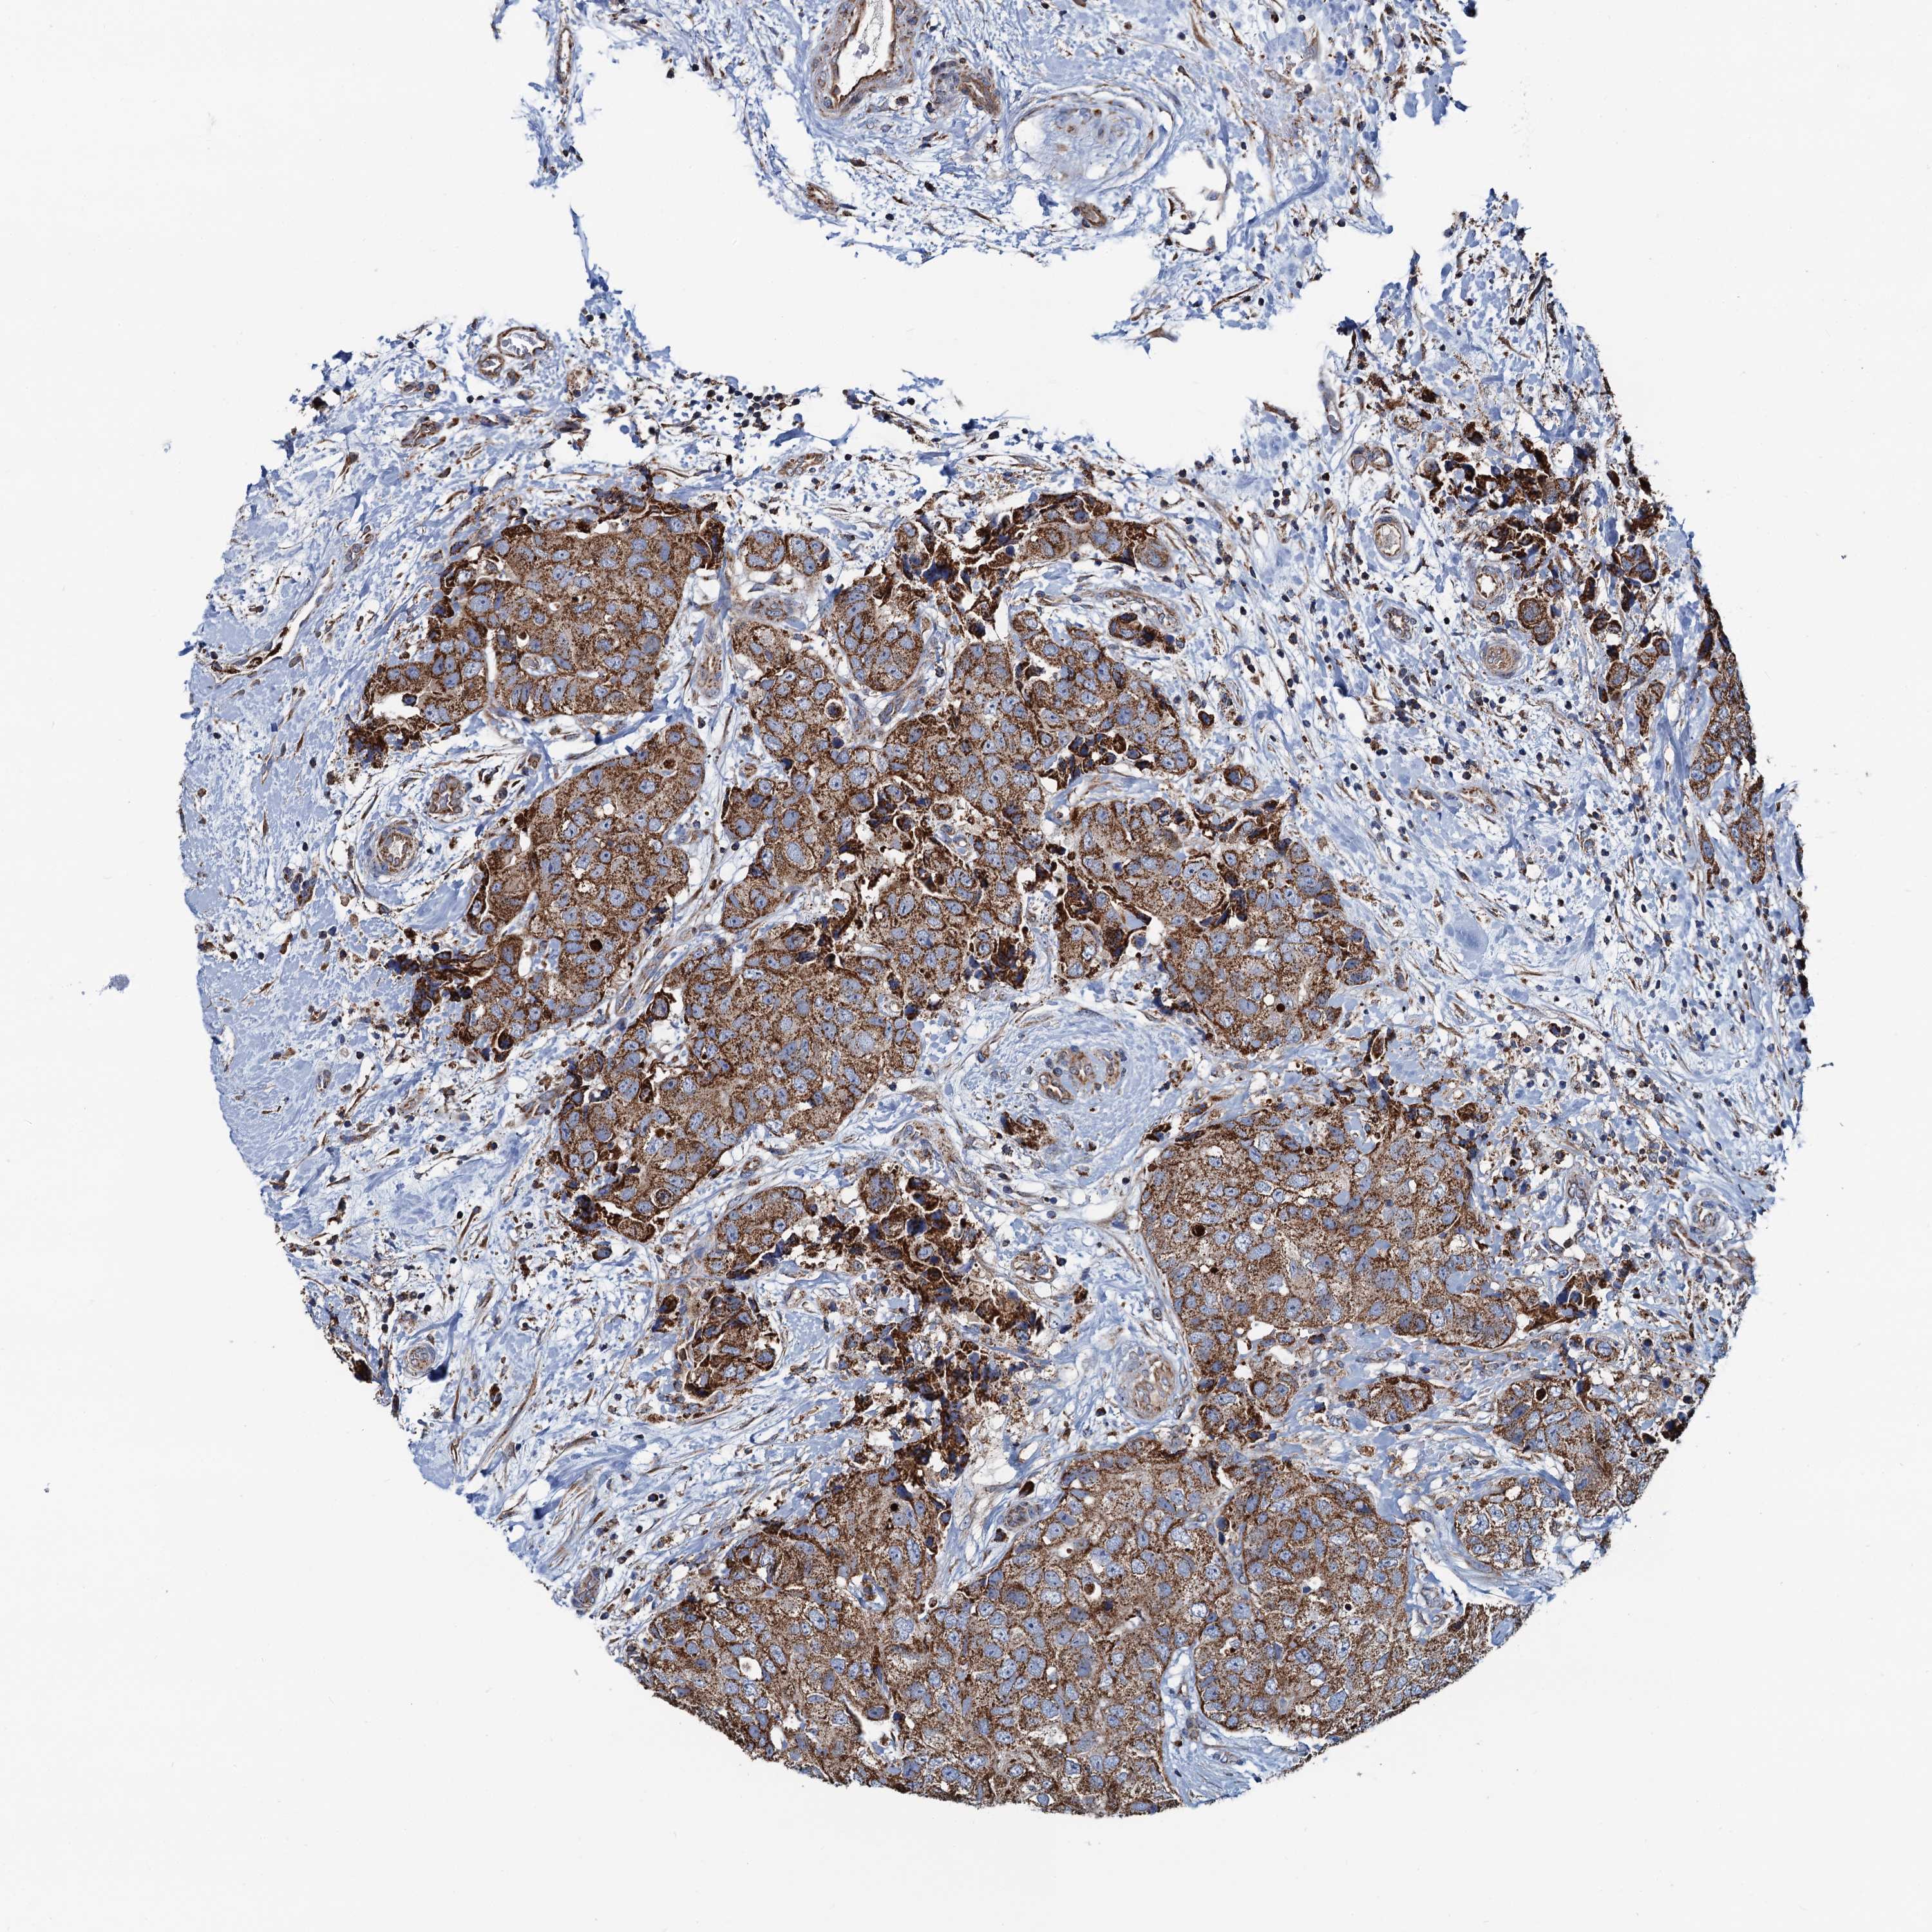

CANCER BREAST CANCER Show tissue menu

BRCA TCGA BRCA VALIDATION PROTEIN EXPRESSION